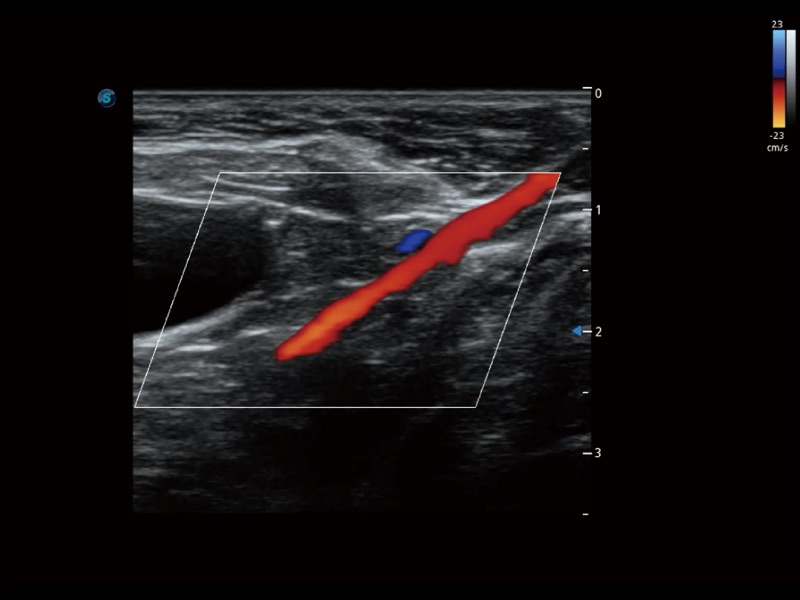

• Micro F 显微血流成像

通过创新的 Matrix E自适应滤波器和超长时间域算法,极大提升超低速微细血流的检出能力,同时更精准地滤除软组织和噪声信号,为兽用医生提供以往无法通过常规血流获得的疾病诊断信息。

• 宽景成像

通过色彩血流和实时宽景相结合,可观察到完整的静脉或动脉的血流,方便医生检查。实时扫查过程中,如有任何操作失误也可以很容易地进行回扫擦除,而不会中断扫查。

(犬)肾脏显微血流

(犬)髂动脉血流